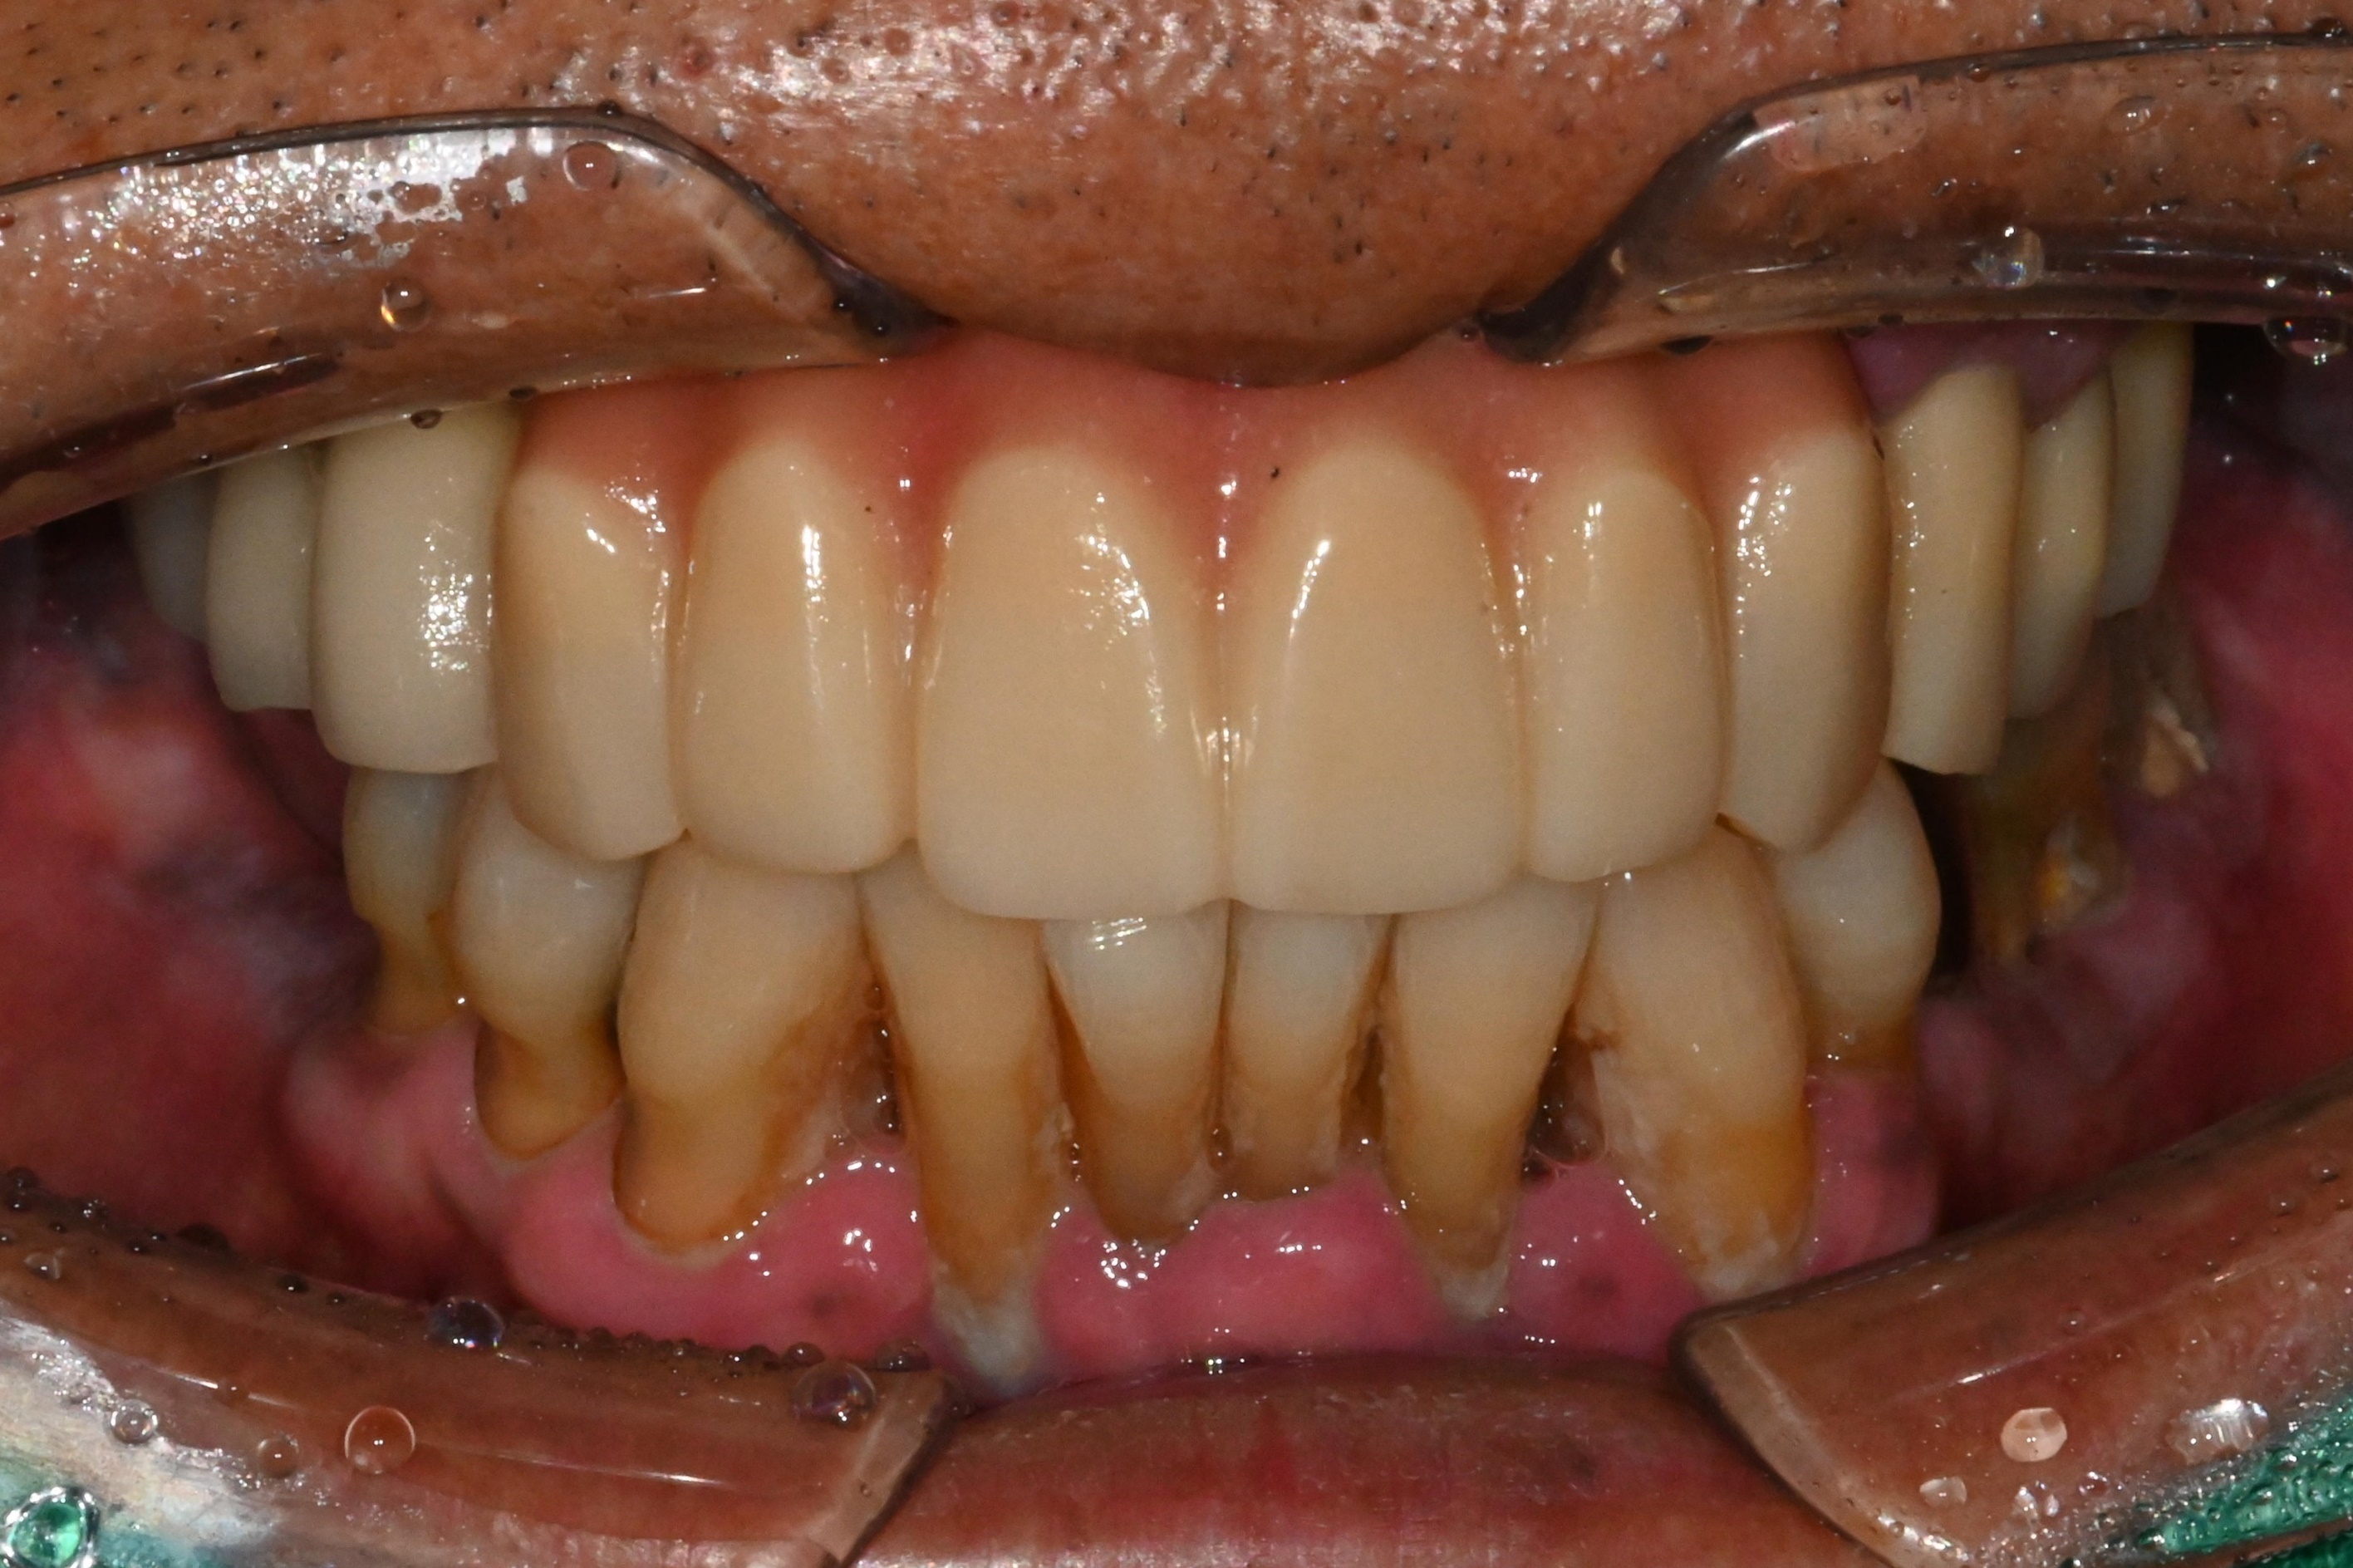

수술 전 후 사진을 비교해보면

더욱 명확히 들어납니다.

보통 치아를 바로 장착할 때는

시멘트를 사용하는 경우가 많은데,

이 시멘트가 잇몸 속에 남으면

염증을 유발할 수 있습니다.

그렇기에

시멘트 없는 구조로

장착하였습니다.